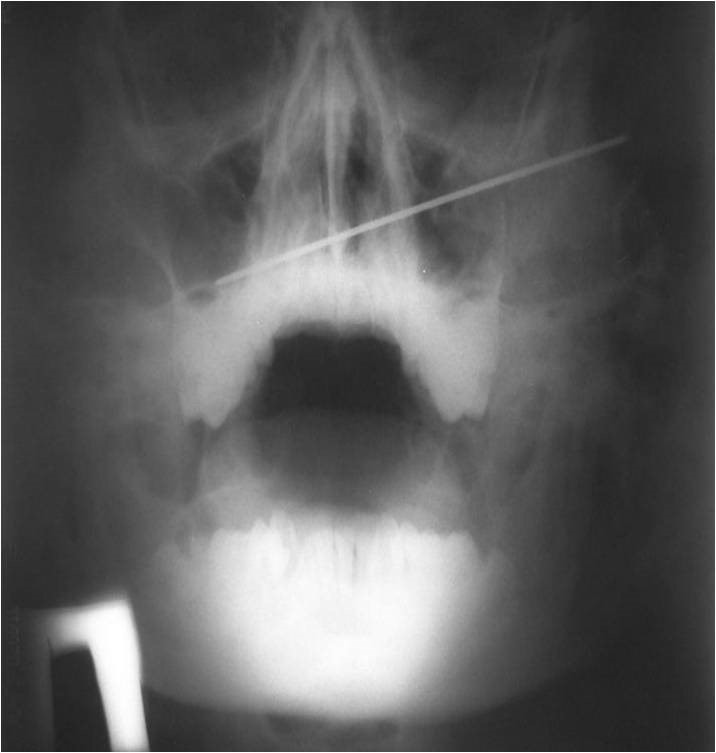

2315. На рентгенограмме у пациента с травмой челюстно-лицевой области спицей киршнера зафиксирована